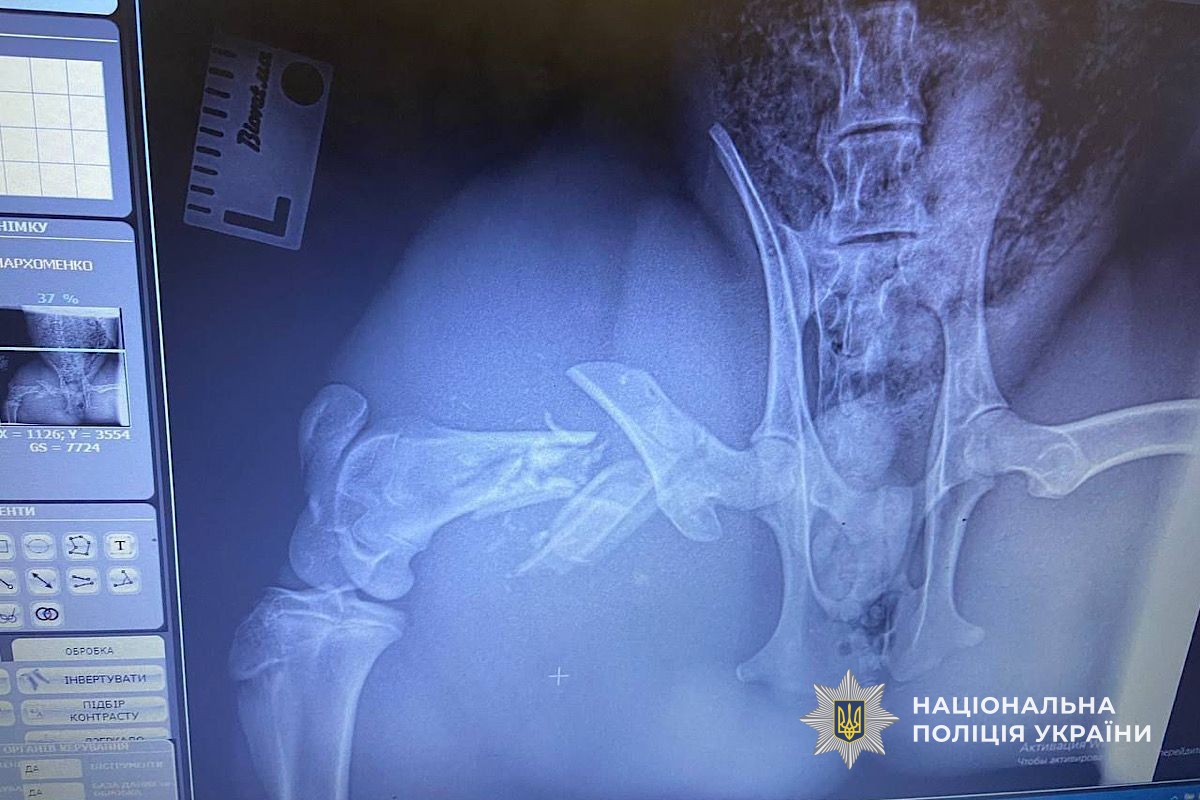

Правоохранители осторожно переместили ее в свой автомобиль и отвезли в ветеринарную клинику. Оказалось, что вследствие удара животное получило переломы.